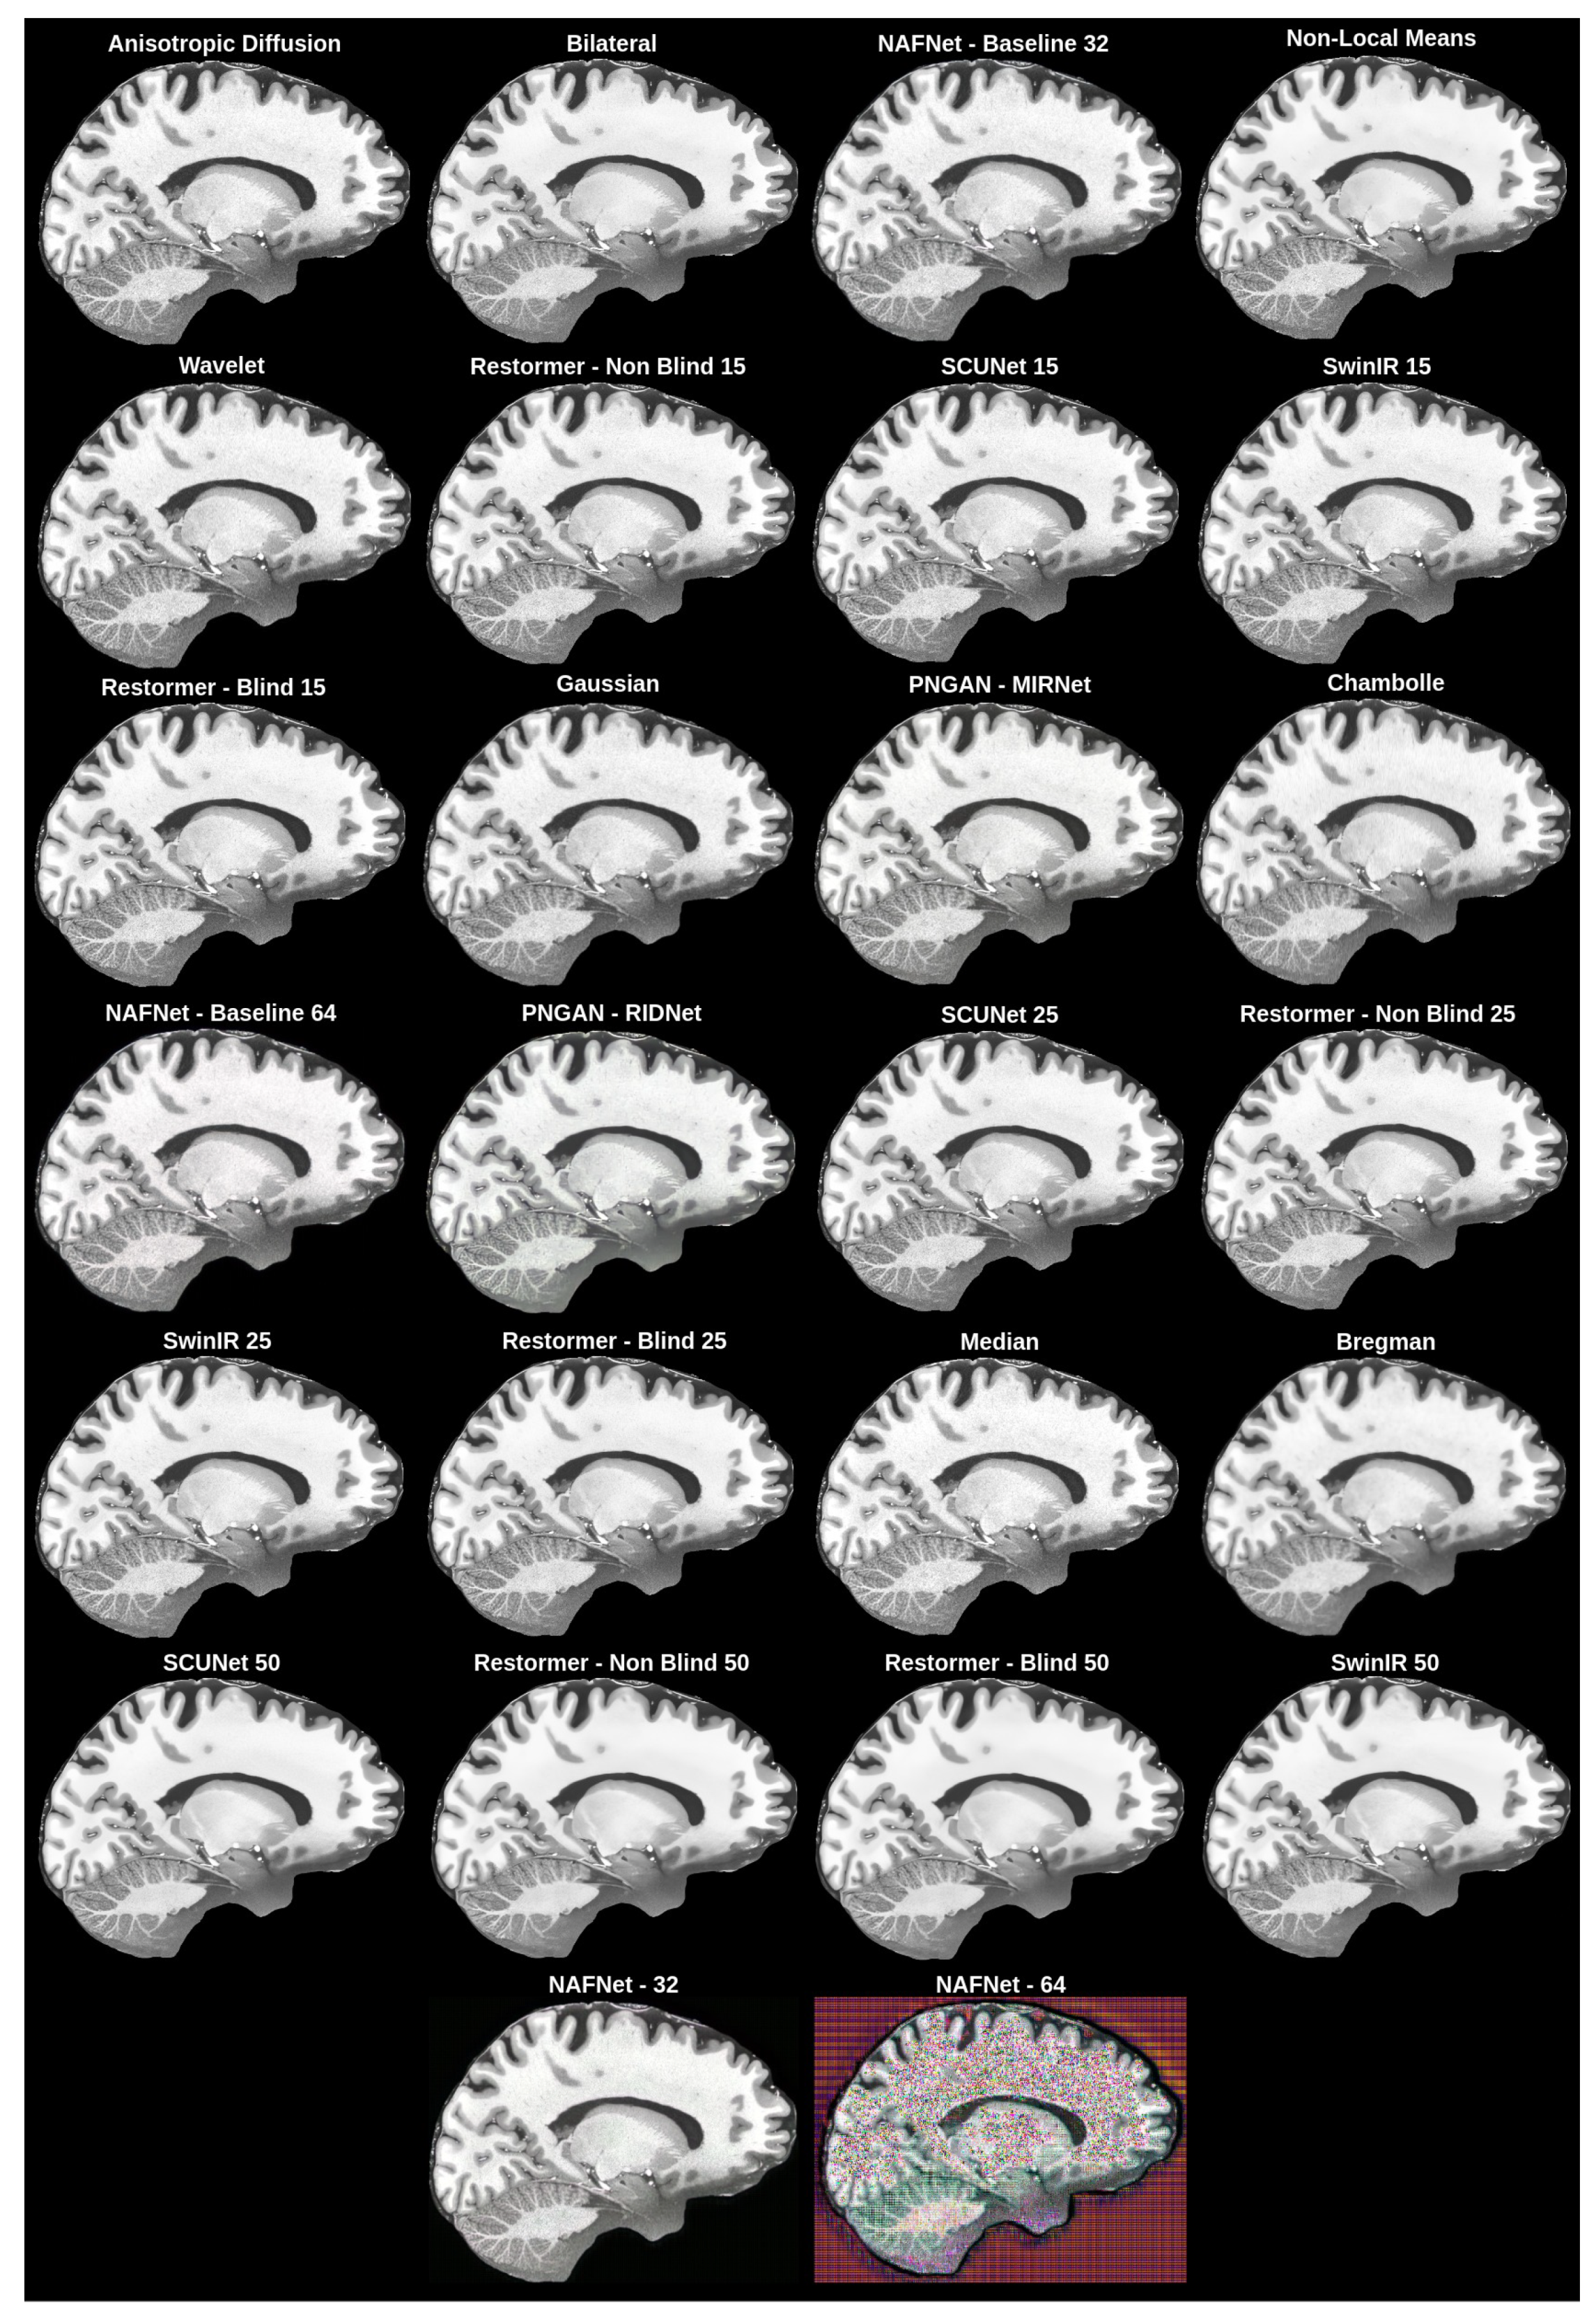

| Model | Modification | SSIM (%) ↑ | PSNR (dB) ↑ | VSI ↑ | LPIPS ↓ |

|---|---|---|---|---|---|

| Anisotropic diffusion | Kappa = 60, gamma = 0.0135 | 99.57 | 45.07 | 0.9992 | 0.0048 |

| Bilateral filter | 98.55 | 39.31 | 0.9943 | 0.0209 | |

| NAFNet | Baseline and width 32 | 97.85 | 36.55 | 0.9978 | 0.0305 |

| Non-local means | 96.25 | 38.44 | 0.9958 | 0.0487 | |

| Wavelet filter | Wavelet = “sym9” | 96.22 | 34.72 | 0.9984 | 0.0631 |

| Restormer | Non-blind and | 96.19 | 35.34 | 0.9970 | 0.0349 |

| SCUNet | 96.18 | 35.35 | 0.9964 | 0.0348 | |

| SwinIR | 96.12 | 35.36 | 0.9965 | 0.0376 | |

| Restormer | Nlind and | 96.09 | 35.31 | 0.9966 | 0.0364 |

| Gaussian filter | Std = 0.75 | 95.96 | 34.14 | 0.9979 | 0.0489 |

| PNGAN | MIRNet | 95.81 | 35.23 | 0.9974 | 0.0587 |

| Chanbolle filter | Weight = 0.08 | 95.11 | 34.84 | 0.9969 | 0.0886 |

| NAFNet | Baseline and width 64 | 94.87 | 34.38 | 0.9976 | 0.1555 |

| PNGAN | RIDNet | 94.08 | 34.09 | 0.9971 | 0.0833 |

| SCUNet | 93.94 | 33.29 | 0.9949 | 0.0553 | |

| Restormer | Non-blind and | 93.85 | 33.24 | 0.9949 | 0.0580 |

| SwinIR | 93.79 | 33.28 | 0.9947 | 0.0636 | |

| Restormer | Blind and | 93.78 | 33.24 | 0.9947 | 0.0577 |

| Median filter | Kernel size = 2 | 93.71 | 30.12 | 0.9947 | 0.0384 |

| Bregman filter | Weight = 4.5 | 91.46 | 32.02 | 0.9949 | 0.0991 |

| SCUNet | 91.07 | 31.19 | 0.9903 | 0.0903 | |

| Restormer | Non-blind and | 90.76 | 31.09 | 0.9899 | 0.0995 |

| Restormer | Blind and | 90.68 | 31.09 | 0.9898 | 0.1013 |

| SwinIR | 90.38 | 31.13 | 0.9904 | 0.1157 | |

| NAFNet | Width 32 | 17.83 | 21.38 | 0.9796 | 0.5353 |

| NAFNet | Width 64 | 16.78 | 15.00 | 0.9349 | 0.5685 |